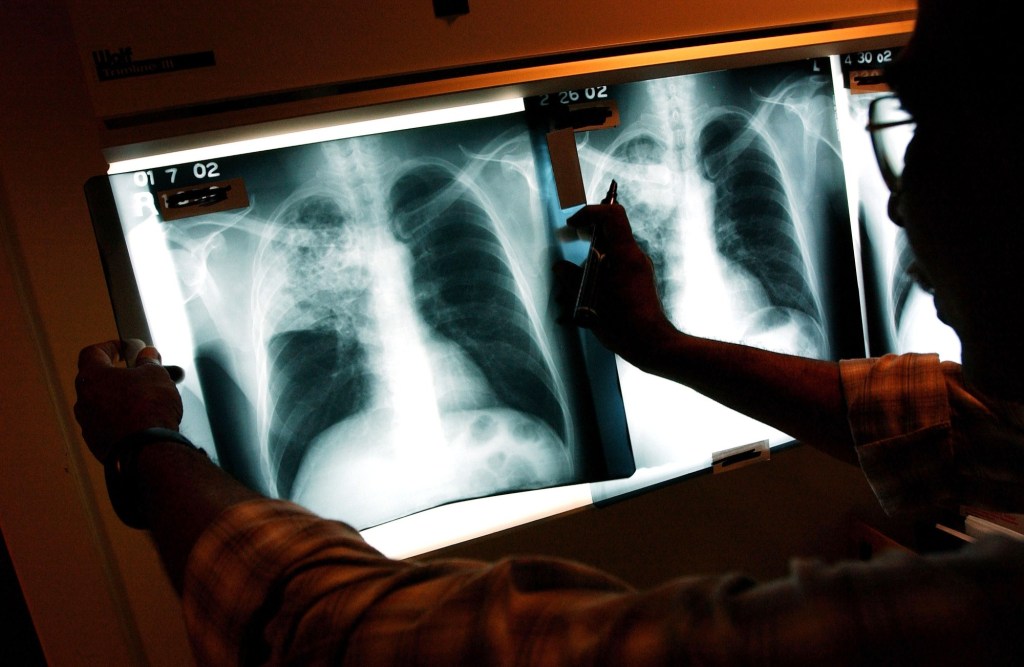

Embora o debate público sobre a questão se tenha centrado nos dólares e nos défices, os riscos são, na verdade, muito maiores: o acesso a uma cobertura de saúde abrangente pode determinar se as pessoas vivem ou morrem.

Mas os depósitos da HSA não fazem nada para evitar os danos reais. As consequências para a saúde da perda do seguro – ou de ter um seguro difícil de utilizar a preços acessíveis – estão bem documentadas. Um conjunto substancial de pesquisas mostra uma relação clara entre a falta de cobertura abrangente e taxas de mortalidade mais elevadas.

Por que o seguro saúde abrangente é tão importante? Existem várias maneiras comprovadas de melhorar a saúde com uma cobertura significativa.

Uma delas é a capacidade de procurar atendimento oportuno quando algo parece seriamente errado. Estudos mostram que as pessoas sem cobertura muitas vezes atrasam ou evitam ir ao hospital quando apresentam sintomas graves, como dor no peito ou falta de ar, devido ao custo. Estes atrasos podem ser mortais: o tratamento atempado de ataques cardíacos, AVC e outras emergências é uma das formas mais consistentes de o seguro reduzir a mortalidade.

Mesmo quando as emergências são cobertas após a franquia, o facto de os pacientes terem de pagar milhares de dólares do próprio bolso leva muitos a evitarem completamente a procura de cuidados de saúde – e planos catastróficos amplificariam este efeito. Estudos de planos de saúde com franquias elevadas mostram que os inscritos atrasam a avaliação da dor no peito, evitam os serviços de emergência devido a sintomas preocupantes e apresentam resultados piores em ataques cardíacos e crises diabéticas.

O seguro também desempenha um papel crucial na detecção de doenças graves enquanto ainda são tratáveis. As pessoas são muito mais propensas a procurar cuidados preventivos quando o seguro os torna acessíveis (ou, como a nossa própria investigação descobriu, quando os seguros os tornam gratuitos). Um estudo da JAMA Oncology com 177.075 mulheres descobriu que aquelas sem seguro privado tinham muito mais probabilidade de serem diagnosticadas com cancro em fase avançada, resultando em taxas de sobrevivência muito mais baixas do que as mulheres com cobertura abrangente.